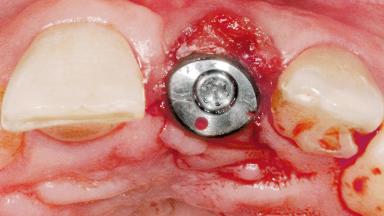

Late Flapless Placement of an Implant in a Maxillary Left Central Incisor Site

Anthony Sclar

Type of Implants One-Piece

Attachment One-Piece

Soft Tissue Grafting Simultaneous